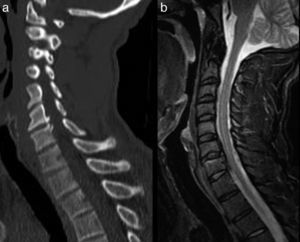

Clinical symptomsPatients with SCIWORA have a wide range of clinical manifestations, from mild, transitory symptoms or deficits (e.g. paraesthesia), to tetraparesis or tetraplegia. Some patients only experience symptoms at the time of trauma, while in others, the neurological deficits only become apparent some days later.1 One element of paramount importance is that large-scale traumas are not specified, since, particularly in adults, there may be cofactors (co-causes) which justify the spinal cord damage. For example, cervical arthrosis or canal stenosis (Fig. 1). This often violates the medico-legal criterion of proportionality. Another characteristic is that these patients do not always exhibit neurological symptoms, or these may be subtle or not expertly assessed. Consequently, they may erroneously be considered as minor cervical injuries (according to Law 35/2015).

MRI of cervical column with STIR sequences (a) and T2 (b and c) in sagittal planes. An inversion of the cervical lordosis with advanced degenerative disco-vertebral changes in C3 to C7 can be discerned (thick arrows in b) and a significant stenosis of the central canal at C4 and C5 level (arrows in b). In the STIR sequence, no bone marrow oedema is noted even in the soft tissue which may suggest an acute lesion (a). Nonetheless, in the T2 sequence, a hypersignal can be made out in the spinal cord at C4–C5 level (arrow in c), consistent with a spinal cord oedema (Kulkarni pattern II). Clinically: previous normality. Occipital pain and paraesthesia in all 4 limbs subsequent to abrupt hyperextension mechanisms. Upon examination: spastic tetraparesis and gait ataxia.